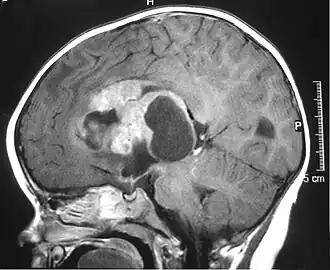

Als atypischer teratoider/rhabdoider Tumor, häufig auch als ATRT oder AT/RT abgekürzt, wird ein seltener Hirntumor aus der Gruppe der embryonalen Tumoren bezeichnet. Der äußerst bösartige Tumor wird nach der WHO-Klassifikation der Tumoren des zentralen Nervensystems als Grad IV eingeteilt und tritt ganz überwiegend bei Kleinkindern auf.

Atypische teratoide/rhabdoide Tumoren können in der hinteren Schädelgrube lokalisiert sein, treten aber auch im Bereich der Großhirnhemisphären auf. Die klinische Symptomatik ist abhängig von der Tumorlage und dem Alter des Kindes und wird in der Regel durch das rasche Tumorwachstum geprägt. Schläfrigkeit, Übelkeit und Erbrechen sind häufige, aber unspezifische Symptome.